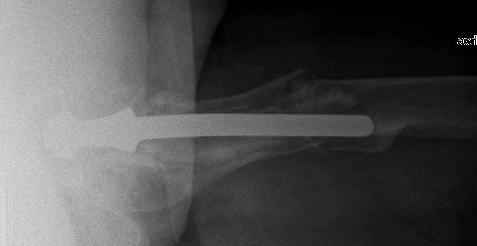

I would like to ask one little question, you said 'tight fit of the nail' to the femoral stem, since all the rotational stability of the system (distal fragment with nail and locking screws) comes from that point, is it reliable?.

The nail tip is jammed. Since it is conical, it can only be jammed more with axial load.

I'd say yes because we use same 6 mm screws for femoral nailing and allow immediate weight-bearing regardless of fracture pattern.